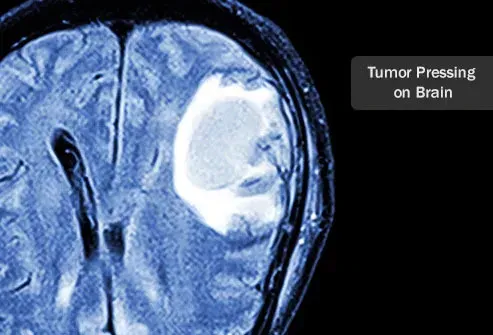

Опасности от мозъчен тумор

Черепът е твърда рамка на костите. Туморите в мозъка са опасни, защото притискат области на мозъка, докато растат. Черепът не е в състояние да се разшири, за да побере наличието на тумор. Когато туморът расте, той натиска мозъка. В зависимост от това коя зона на мозъка е засегната, това може да доведе до проблеми с мисленето, действащо и усещане. Фактори, които определят колко опасен е мозъчният тумор, включват местоположението дали може да бъде отстранен хирургично и колко бързо расте и дали има способността да се разпространява или не.